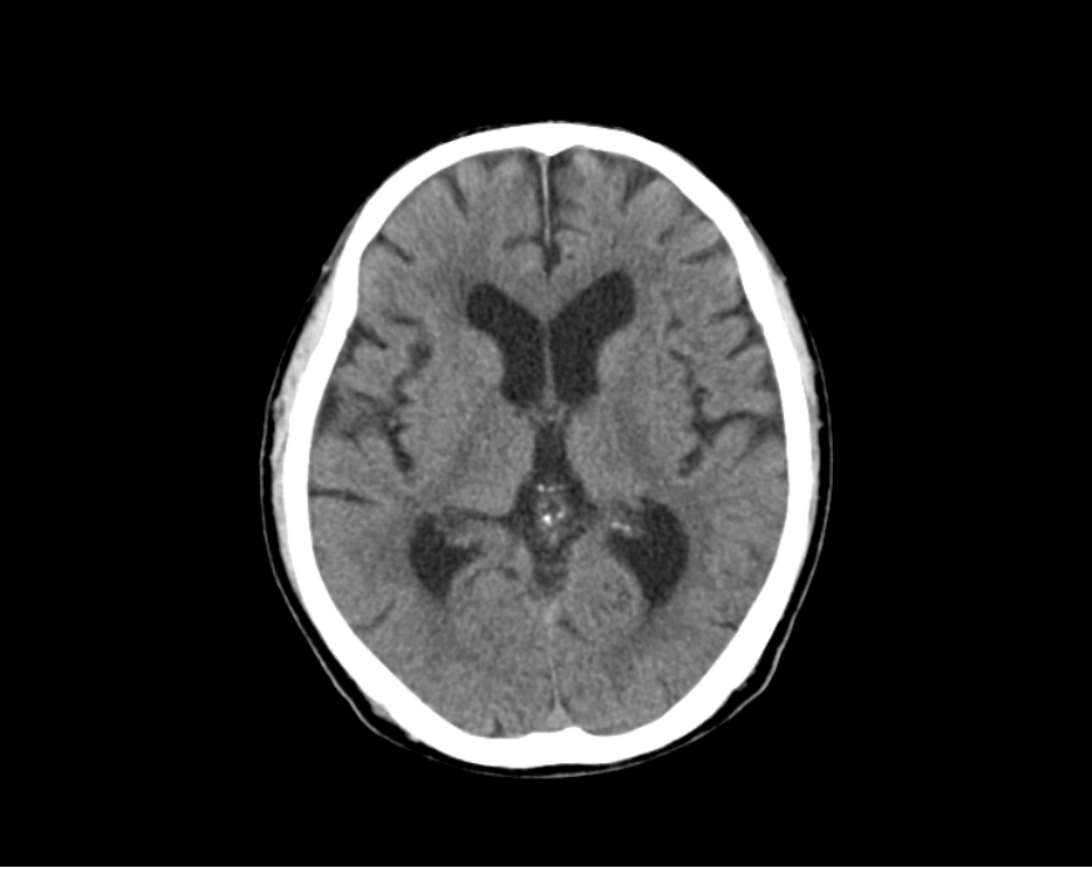

CT Aquilion lightningの導入

当院では新しいCTを導入いたしました。

高速マルチスライスでの撮影によって、従来のCT検査よりも短い時間で検査を受けることが出来ます。

撮影の際、体の部位に対して最適線量での撮影を自動調整できるため、被ばく低減が可能になりました。

新しいCTでは開口径を780㎜と広くすることによって狭い場所が苦手な方でも安心して検査を受けていただけます。